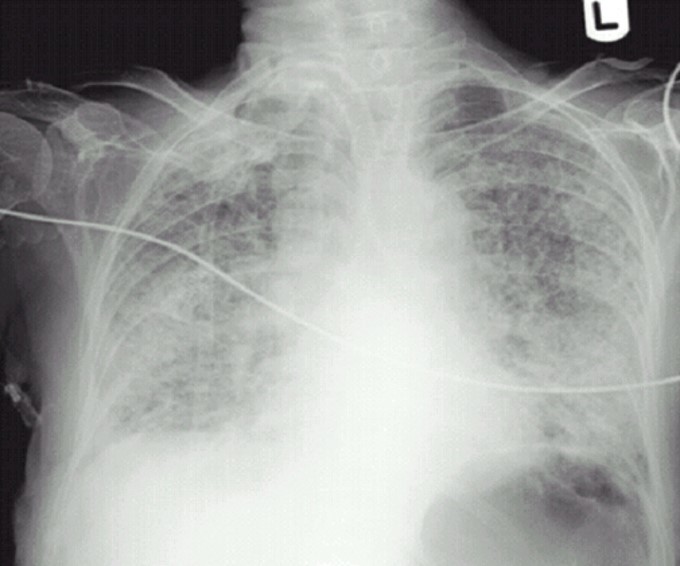

What is seen here?

Lung Bullae/Bleb

Spnt Pneumothorax

Acute Respiratory Distress Syndrome

ARDS

Left Tension Pneumothorax

Flattening of left diaphragm

Deviated to the right